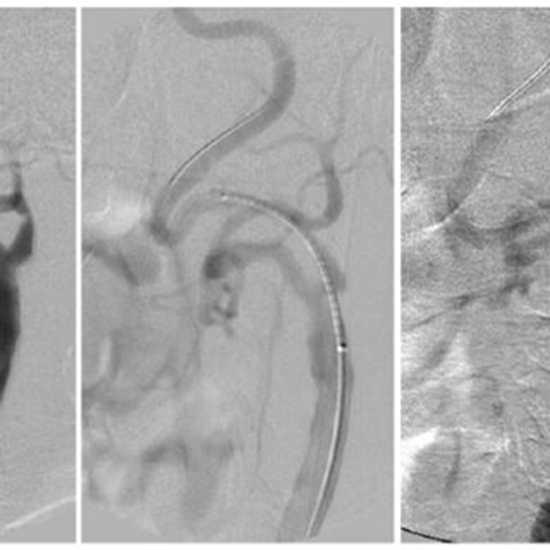

Efficacy of Carotid Artery Stenting Without Embolic Protection Device for Carotid Stenosis: A Retrospective Cohort Study from a Major Neurointerventional Center

Methods: This retrospective cohort study analyzed all patients with internal carotid artery (ICA) stenosis who underwent CAS at a single neurointerventional center from January 2016 to September 2022. Patients with concurrent intracranial stenosis, previous CEA, interfering neurological disorders, or incomplete data were excluded. Preoperative evaluations included comprehensive clinical assessments, and CAS procedures were conducted without embolic protection devices (EPDs). Postoperative monitoring involved intensive care unit (ICU) observation and MRI in selected cases.

Results: The study included 91 patients (mean age 69.2±10.2 y, 65.9% male). The right ICA was involved in 46 patients and the left in 45 patients. The degree of stenosis significantly decreased from 80.58±12.53% to 16.61±9.54% post-CAS. Early neurological complications were observed in 5.4% of patients. Transient bradycardia during the procedure was common but resolved with atropine. One patient experienced prolonged bradycardia, but it resolved without lasting effects. Two patients had transient contralateral paresis postprocedure; one showed diffusion restriction on MRI but both recovered fully. Severe complications included one death due to intracranial hemorrhage and one case of hemiplegia with partial recovery over 3 months. Follow-up ultrasound in 30 patients showed no instances of restenosis.

Conclusions: CAS significantly reduces CS and potentially aids in stroke prevention. The findings suggest that CAS without EPDs may achieve similar early outcomes, particularly in regions with limited EPD access.